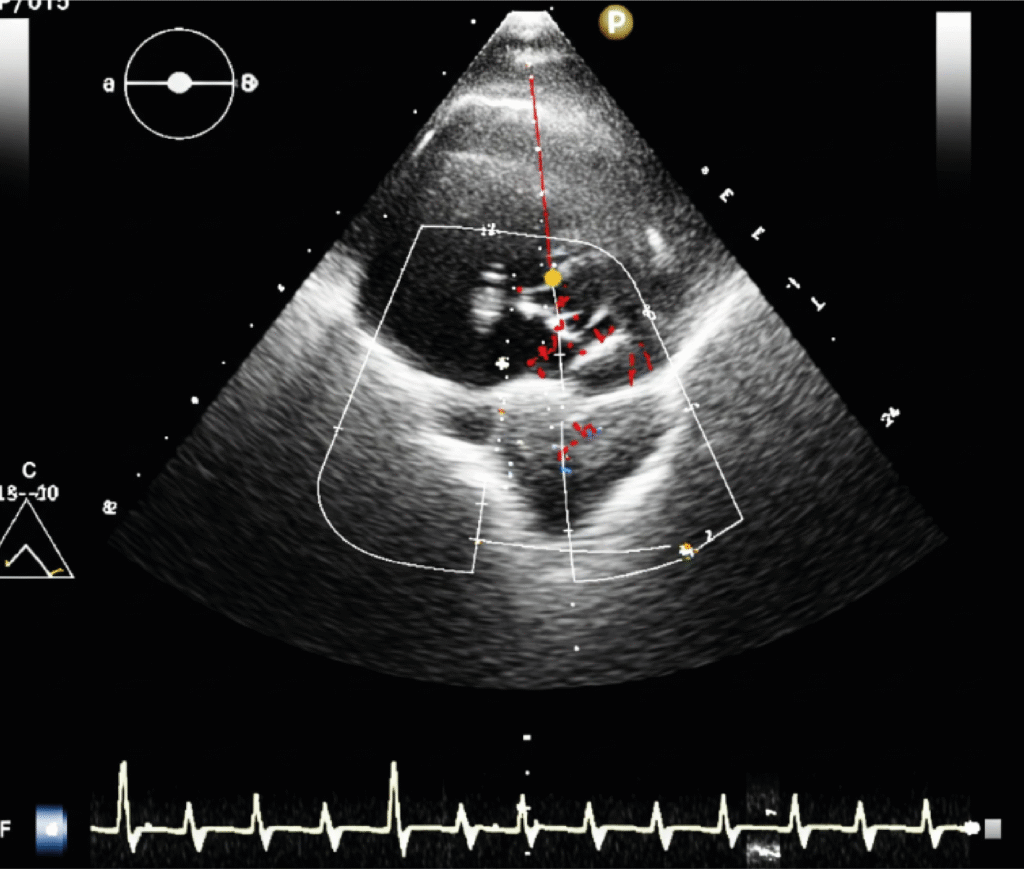

Transthoracic,

Transesophageal And

Intraoperative Echocardiography

Advanced echocardiographic techniques used to assess heart structure and function with unmatched clarity. Whether through the chest wall, esophagus or during surgery, each method delivers critical real-time cardiac insights.